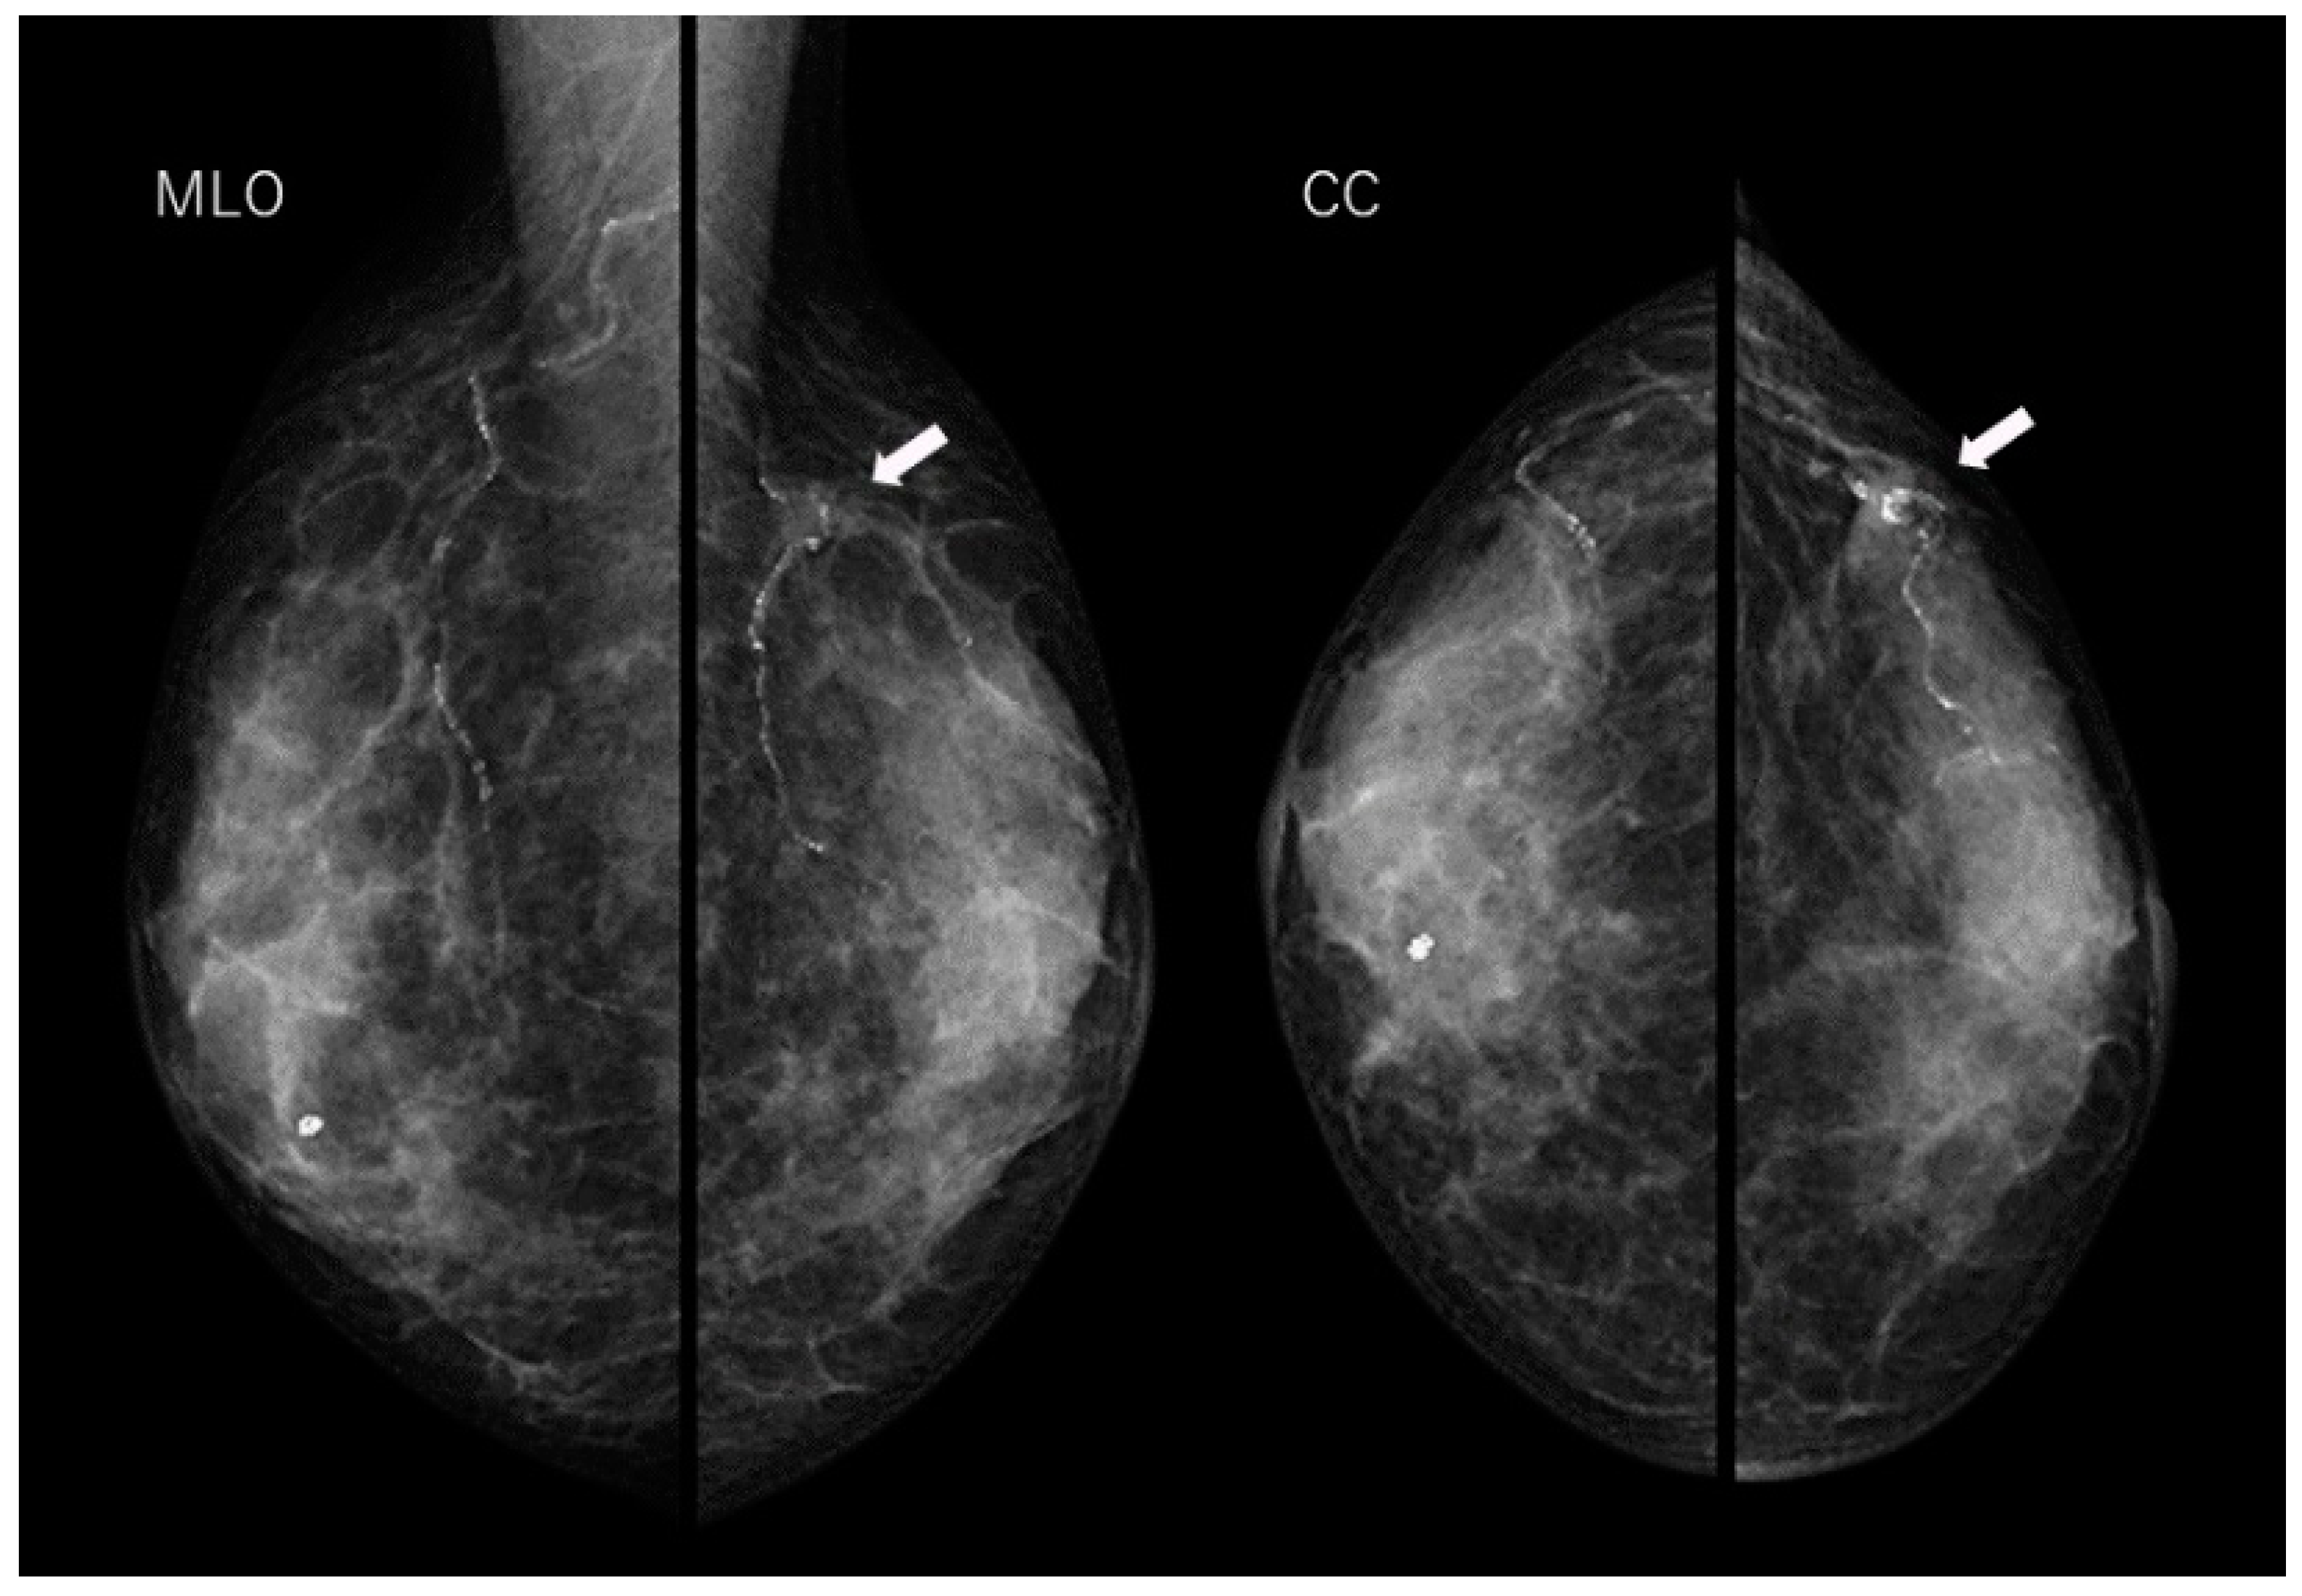

Arterial Calcification Disappearance in Breast Imaging: A Key Indicator for Transition to Invasive Ductal Carcinoma

Sato, A.; Fujioka, T.; Onishi, I.; Yamaga, E.; Katsuta, L.; Kubota, K.; Kumaki, Y.; Ishiba, T.; Oda, G.; Tateishi, U. Arterial Calcification Disappearance in Breast Imaging: A Key Indicator for Transition to Invasive Ductal Carcinoma. Diagnostics 2024, 14, 727. https://doi.org/10.3390/diagnostics14070727